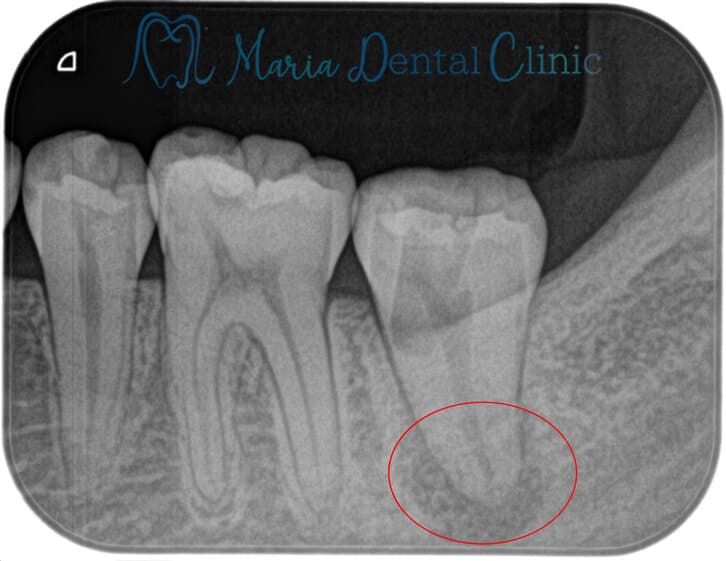

レントゲンの画像

根管治療が必要な根尖性歯周炎のレントゲン画像|東京 目白マリア歯科

噛むと痛い、歯茎を押すと痛い、膿が出てくる(瘻孔・フィステル)など根尖性歯周炎の症状がある場合は、再根管治療が必要です。

しかし、レントゲンで根尖性歯周炎が確認できる場合でも、約7割の患者様には自覚症状がありません。ご自身が知らない間に進行していることも多く、無症状のため歯科医院でのレントゲンによる検診で指摘されることがほとんどです。

2. 1の症状は確認できないが、レントゲンで根尖性歯周炎が確認できる場合